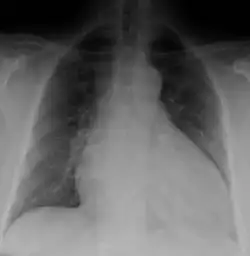

Diagnosis

Generalized enlargement of the heart is seen upon normal chest X-ray. Pleural effusion may also be noticed, which is due to pulmonary venous hypertension.[28]

The electrocardiogram often shows sinus tachycardia or atrial fibrillation, ventricular arrhythmias, left atrial enlargement, and sometimes intraventricular conduction defects and low voltage. When left bundle-branch block (LBBB) is accompanied by right axis deviation (RAD), the rare combination is considered to be highly suggestive of dilated or congestive cardiomyopathy.[29][30] Echocardiogram shows left ventricular dilatation with normal or thinned walls and reduced ejection fraction. Cardiac catheterization and coronary angiography are often performed to exclude ischemic heart disease.[28]